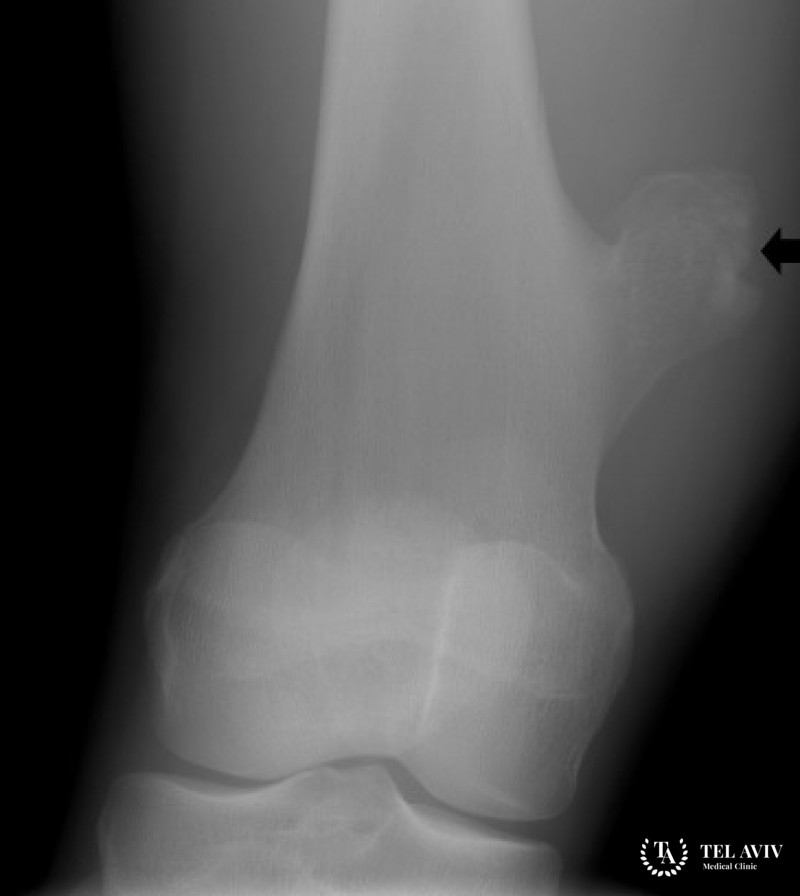

- Рентген. Если во время пальпации врач обнаруживает новообразование на кости пациента, то он отправляет его на рентген. На рентгеновских снимках при наличии данного недуга может обнаруживаться нарушение контуров кости.